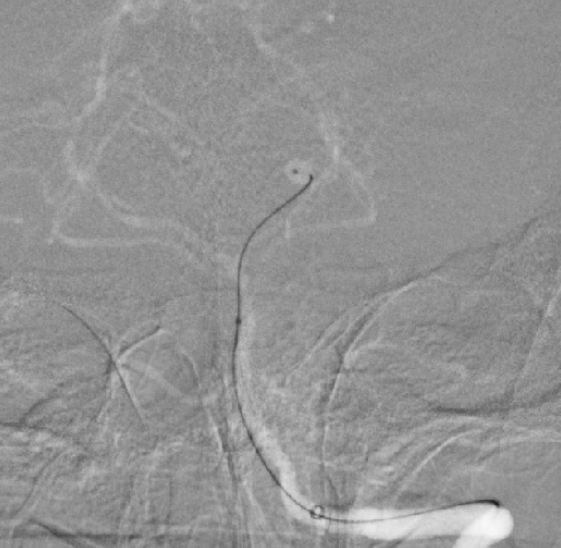

??术中造影见左侧大脑后动脉纤细

??术中微导管到位